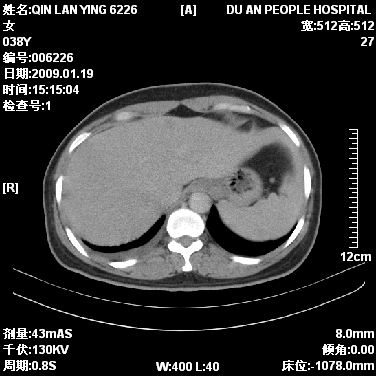

标题: CT17781:女,38岁,胸疼1个月。

女,38岁,胸疼1个月。wbc:1万4

1)右肺中央型肺癌并右肺上叶阻塞性肺炎、节段性肺不张,纵隔淋巴结转移、右侧胸膜转移、肝脏转移。2)右侧胸腔少量积液。

1、右侧中央型肺癌并阻塞性肺不张,纵隔内、主动脉弓旁、右肺门淋巴结及肝脏转移可能性大,建议纤支镜进一步检查。

2、右侧胸腔积液。

本病例有几个容易诊断的地方:1、右肺上叶前段支气管闭塞,肺不张。2、淋巴结明显肿大。3、肝脏多个类圆形低密度影呈“牛眼征”改变,高度提示转移。

从影像学角度分析      右肺上叶中央型肺癌,并阻塞性不张、肺炎,纵隔淋巴结、膈顶淋巴结转移。

肝内两个大小不等低密度结节,内可见更低密度影,首先考虑肝内转移瘤,但联想到患者wbc1万4,建议楼主还是做个增强比较明确,除外肝脓肿的可能。